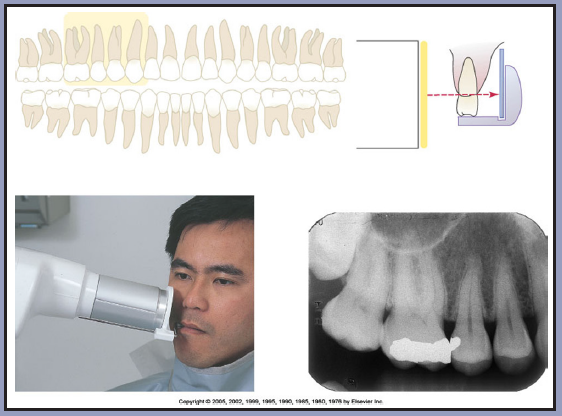

Procedure for the Mandibular Premolars

1. Assemble the posterior receptor holding device and insert the receptor horizontally on the posterior biteblock. Use a type 2 receptor.

2. Center the receptor on the premolars. (Figure 32) The receptor should be parallel with the long axis of the tooth. (Figure 33) The object-to-receptor distance in both the mandibular premolar and molar regions is minimal since the oral anatomy only allows the receptor to be positioned very close to the teeth and still remain parallel. Align the anterior border of the receptor with the canine so that the image captured on the anterior edge of the receptor will be the distal third of the canine. Position the biteblock on the occlusal surfaces of the teeth to be radiographed. Proper positioning in this step will place the central ray of the x-ray beam between the premolars.

3. A cotton roll may be inserted between the maxillary teeth and the biteblock for patient comfort. Ask the patient to slowly but firmly bite onto the block to maintain the correct position. The receptor should be adjusted as the patient closes and the floor of the mouth relaxes.

4. Slide the aiming ring down the indicator rod; it should be as close to the skin as possible without actually touching the patient. Align the tube head close to the aiming ring, and center. (Figure 34)

5. Follow the receptor and equipment manufacturer's recommendation concerning exposure factors. Make the exposure.

6. This procedure should be followed for the opposite side premolars.

Figure 32 – Mandibular Premolars

Figure 32

Figure 33 – Mandibular Premolars

Figure 33

Figure 34 – Mandibular Premolars

Figure 34